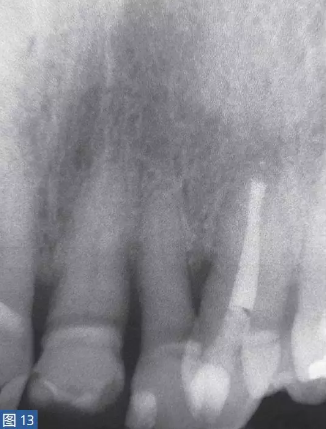

根尖周囊腫(圖12 和13)總是與無(wú)癥狀的根尖周炎相關(guān)。目前普遍認(rèn)為,通過(guò)上皮殘留細(xì)胞的炎性增殖形成了根尖周囊腫。在組織學(xué)上,它們分為袋囊腫(pocket cyst)和根尖周真性囊腫(periapical true cysts)。通常認(rèn)為,袋囊腫可以通過(guò)單純的根管治療而非手術(shù)方式,即通過(guò)細(xì)胞凋亡(apoptosis)和程序性細(xì)胞死亡(programmed cell death)達(dá)到愈合。這種方式在真性囊腫似乎不太可能實(shí)現(xiàn)。

圖12: 23 牙齒根尖周囊腫 。非手術(shù)治療,采取單純的根管治療后的X 線片檢查。因未愈合而決定采取手術(shù)治療。

圖13:手術(shù)性根管治療一年后的對(duì)照X 線片顯示根尖病灶已愈合。對(duì)搔刮出的組織進(jìn)行組織病理學(xué)檢查顯示為真性根尖周囊腫。